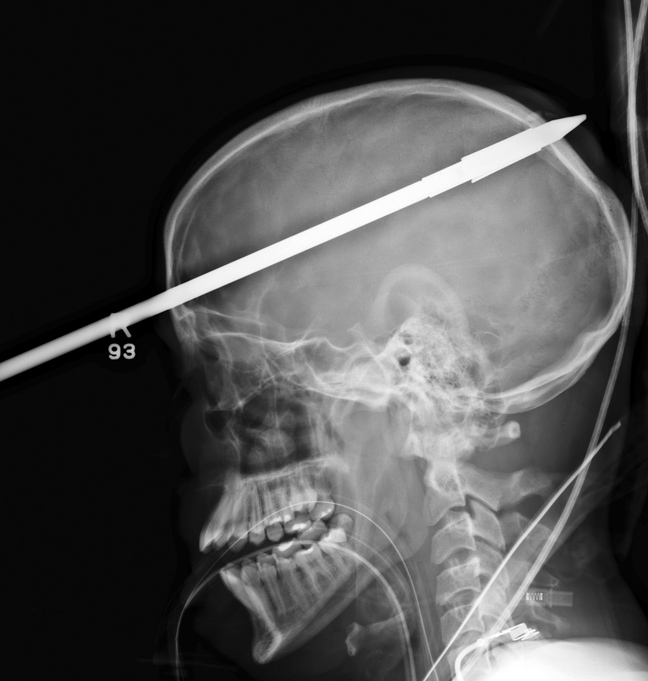

Οι ακτινογραφίες δείχνουν πώς η λόγχη διαπέρασε το κρανίο και τον εγκέφαλο του αγοριού. Ο Yasser Lopez κολυμπούσε με φίλους του σε λίμνη στη Φλόριντα όταν ένας 15χρονος φίλος του κατά λάθος απελευθέρωσε το καμάκι ενώ «όπλιζε» το ψαροντούφεκο.

Το καμάκι χτύπησε τον Lopez μερικά εκατοστά πάνω από το δεξί του μάτι, καρφώθηκε στο κρανίο του και ακινητοποιήθηκε στο δεξί λοβό του εγκεφάλου του. Τα παιδιά σοκαρισμένα είδαν το καμάκι να μπαίνει στο πίσω μέρος του κεφαλιού του και να εξέχει από το μέτωπό του!

Αντίθετα οι γιατροί σταθεροποίησαν το καμάκι και απομάκρυναν κομμάτι μήκους 47 εκατοστών, πριν βγάλουν τις ακτινογραφίες. Χρειάστηκαν στη συνέχεια τρεις ώρες για να απομακρύνουν τη λόγχη από τον Lopez, ο οποίος νοσηλεύεται σε σοβαρή αλλά σταθερή κατάσταση.